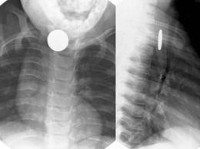

T17.4 Инородное тело в трахее